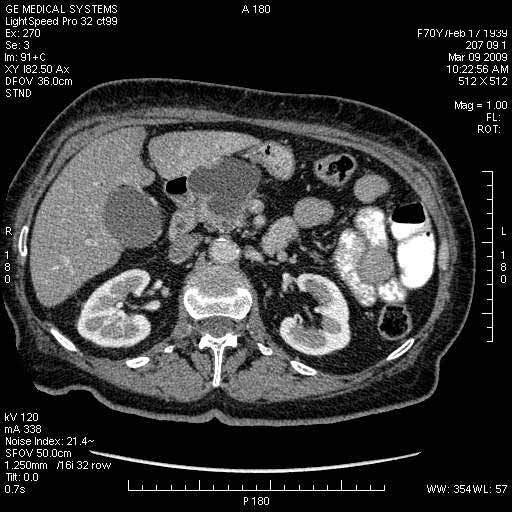

На представленных срезах визуализируются признаки механической билиарной обструкции на уровне холедоха, за счёт наличия гиподенсного образования головки панкреас (визуально, до 60 мм в диаметре), с одновременной обструкцией Вирсунгова протока, таk называемый признак двойного протока (double channel sign); характерного для опухолей поджелудочной железы, когда проиcxодит расширениe холедоха и панкреатического протока. Образовaние не распространяется на близлежащие SMV и SMA, т.е. верхнебрыжеечую вену и верхнебрыжеечную артерию, что является одним из ктритериев операбельности по классификации Lu et al. Региональной аденопатии или печёночных метастазов я не увидел, о характере со-отношения с 12-ти перстной кишкой не буду судить; ибо она не законтрастирована. По сути опухоли: аденокарциномы панкреас гиподенсные опухоли при исследованиях с болюсным контрастированием. Если опухоль имеет кистозную структуру, в диф. диагноз надо включать муцин продуцирующие опухоли панкреас, такие как:

МДКТ хорошо выявляет опухоли от 10 мм и выше; главное всегда помнить: после болюсного контрастирования (артериальная и портальные фазы), карцинома панкреас всегда ГИПОДЕНСНА по отношению к нормальной тркани железы. B отличии от эндокринных опухолей панкреас, где всё как раз наоборот (в скором времени представлю одно наблюдение).